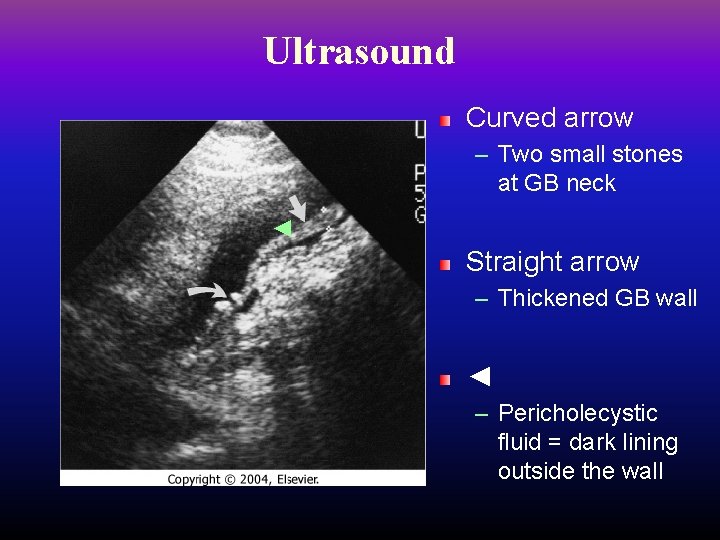

Ultrasound is the first choice for imaging – – Distended gallbladder Increased wall thickness (> 4 mm) Pericholecystic fluid Positive sonographic Murphy’s sign (very specific) Nuclear HIDA scan shows no filling of GB – If U/S non-diagnostic, order HIDA

Ultrasound Curved arrow – Two small stones at GB neck ◄ Straight arrow – Thickened GB wall ◄ – Pericholecystic fluid = dark lining outside the wall